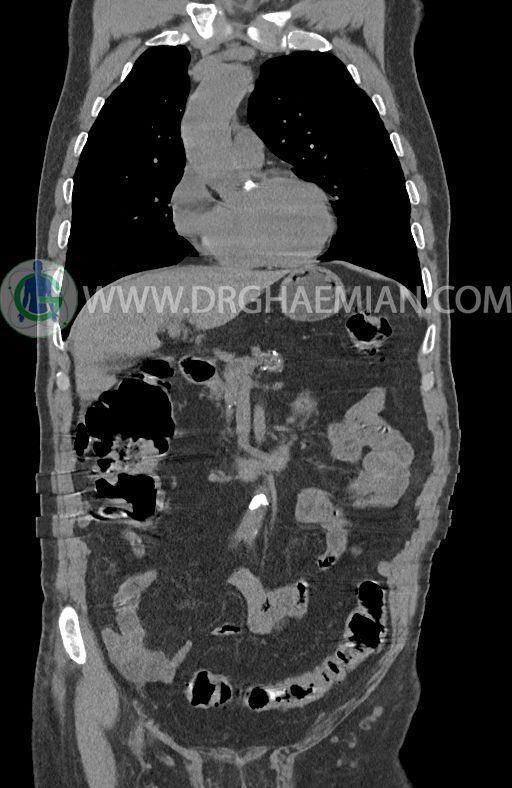

در سی تی اسکن اسپیرال ریه ها و مدیاستن، شکم و لگن با و بدون کنتراست وریدی (مولتی دیدکتور 16 با مقاطع ظریف و بازسازی کرونال) :

–افزایش ضخامت تومورال دیستال مری و GEJ در سگمانی به طول 4cm-5cm (T2 or T3)

-3 لنف نود رژیونال با SAD ≤ 9 mm دیده می شود. (N2)

–آتروفی نسبی پانکراس همراه با فوکوس های کلسیفیه ی منتشر پارانشیم مطرح کننده ی پانکراتیت مزمن

-CBD بسیار دیلاته (16mm) همراه با دیلاتاسیون مجاری داخل کبدی سنترال بدون شواهد سنگ یا توده در مسیر